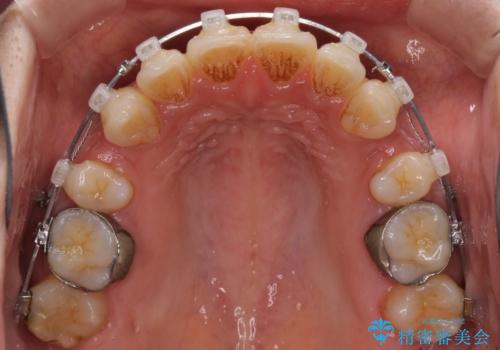

- クリアブラケット

- 2年2ヶ月

上顎の前から両側の前から4番目の歯と、下あごの前歯を1本抜歯して、口元をすっきりさせる計画としました。